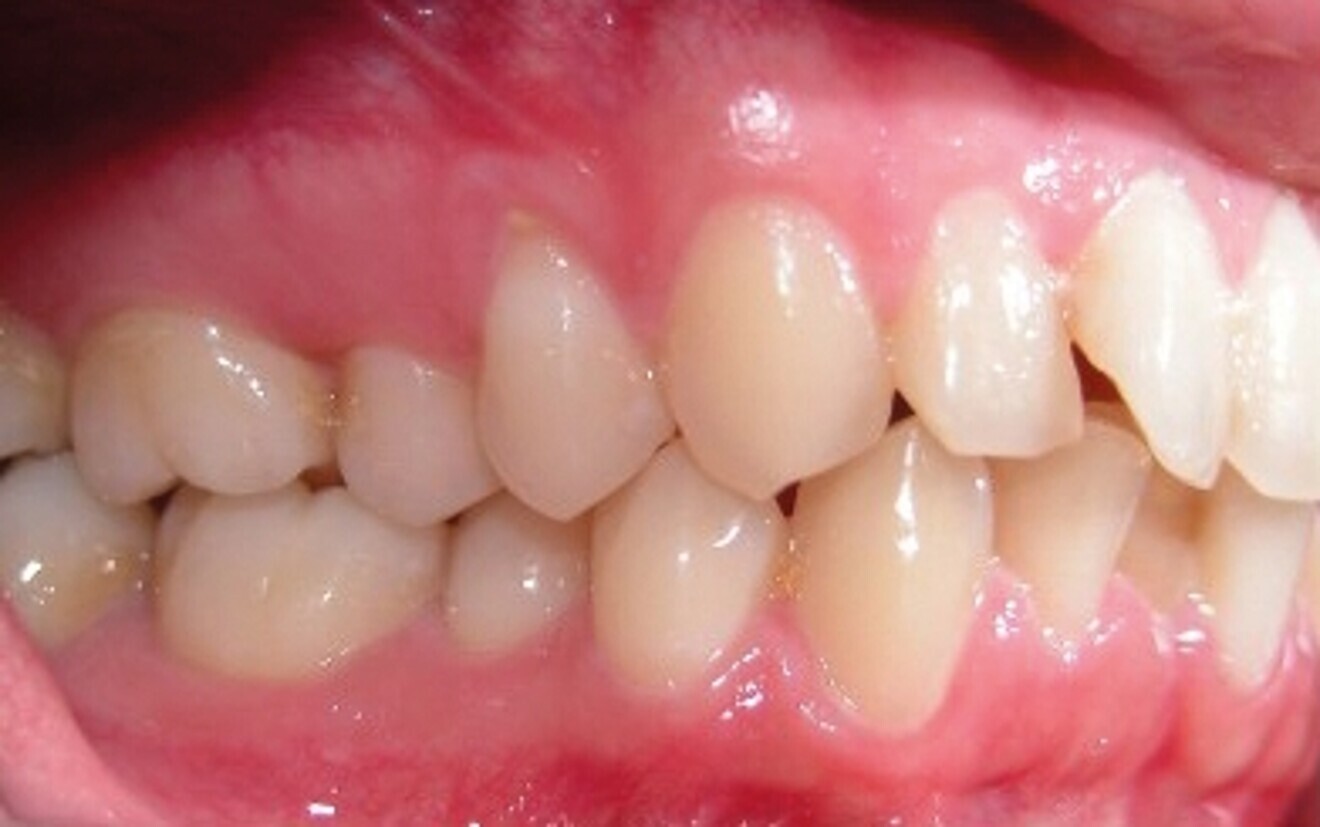

Le motif principal de consultation de la patiente, une jeune femme de 27 ans, est un encombrement dentaire accompagné d’une occlusion mal équilibrée. Danseuse de profession, elle se tracasse énormément au sujet de son apparence lors de ses apparitions publiques si elle entreprend un traitement. L’examen clinique révèle une relation d’Angle de classe I du côté droit et une relation molaire canine de classe II du côté gauche (Fig. 1).

De ce côté, les molaires, les prémolaires et la canine sont en occlusion croisée. L’examen ne montre aucun déplacement latéral fonctionnel de la mandibule. La ligne médiane maxillaire est en harmonie avec la symétrie faciale, mais la ligne médiane mandibulaire est déviée vers la gauche, en raison d’un décalage des dents de 4 mm. On observe un encombrement important des dents inférieures, évalué à 11 mm, et un encombrement modéré de 10 mm au niveau de l’arcade maxillaire. Les racines des dents 31, 33 et 43 semblent proches du rebord vestibulaire de l’os cortical, et les deux arcades présentent un rétrécissement dans la région des prémolaires et molaires.

Fig. 1b : Photographie intraorale initiale.